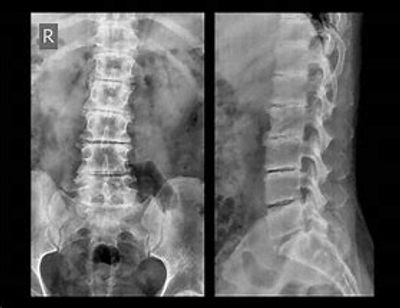

Patient came in last week with acute low back pain. Antalgic posture with forward leaning to the right. He could not stand up. Intense pain and could only walk by shuffling his feet into the office.

He has on and off back reoccurring disc compromise to 5 discs. If he goes to long, say 3-6 months without a tune-up or if he lifts something at work repeatedly in a day, he will tweak the lumbar structure.

Utilizing acupuncture to the local sites and with pain points for 30 minutes, allows the pain to dismissed dramatically. Then we begin corrective protocols for results 3-10 days.

On this occasion, he felt better immediately. And as the night went on and he was pain free in 24 hours. Wow !!!